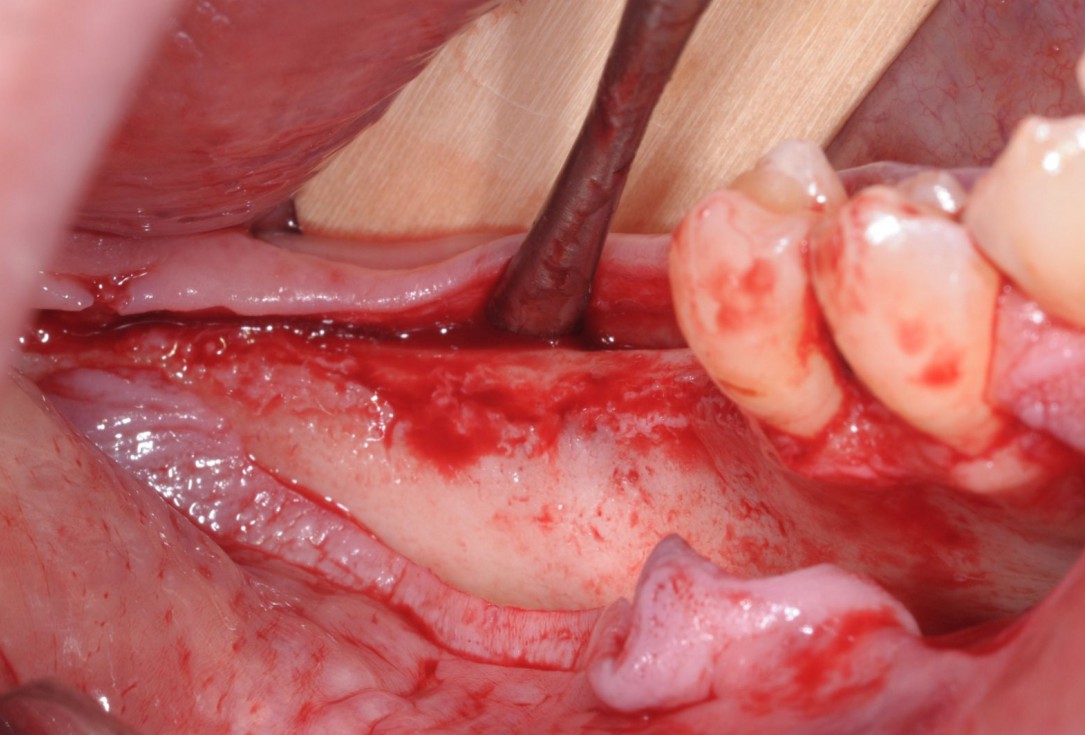

03/28 - Initial clinical situation - massive bone loss in the posterior 4th quadrantThree-dimensional augmentation with maxgraft® cortico - Dr. R. Würdinger